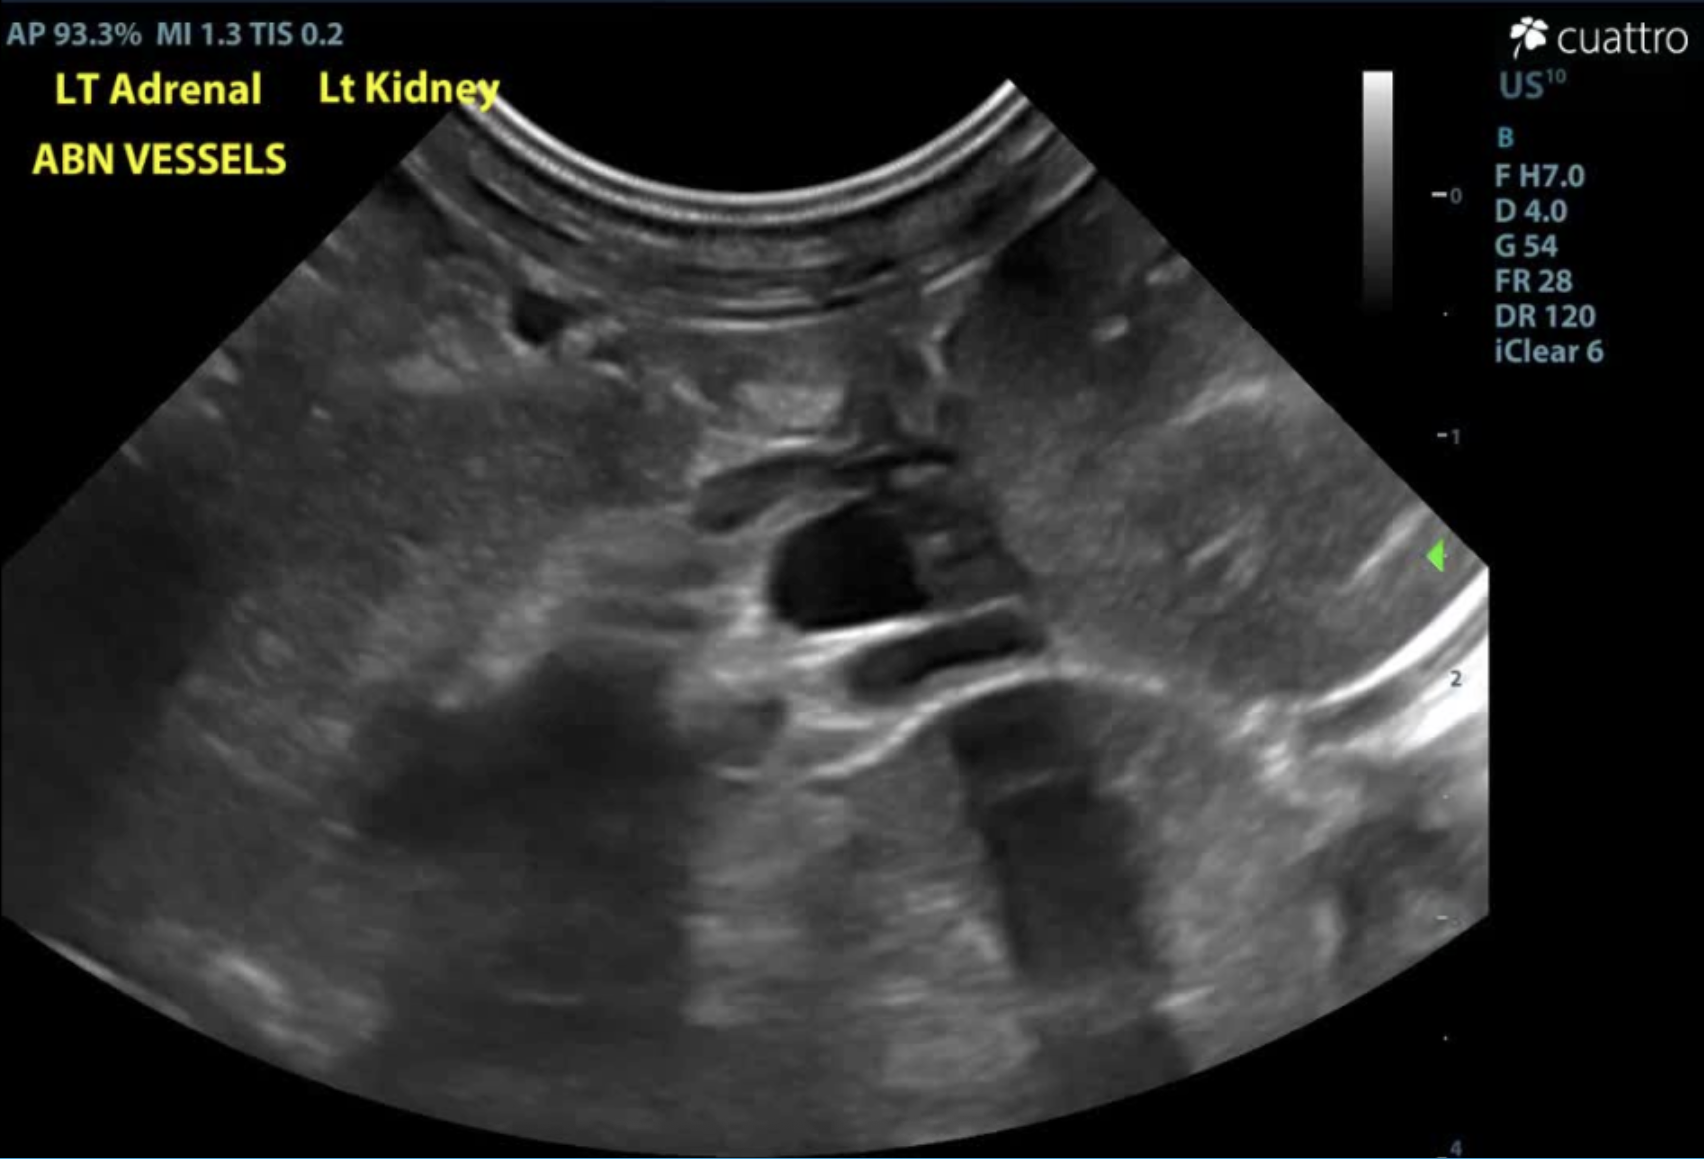

An abnormal vascular pattern is appreciated in the left cranial abdomen which obscures visibility of the left adrenal gland.

Images of irregular, tortuous vessel in the left craniolateral abdomen adjacent to the left kidney and left adrenal gland. (A) images of the vessel without Doppler coloration vs. (B) with Doppler to highlight vascular structures and the irregular pattern formation.